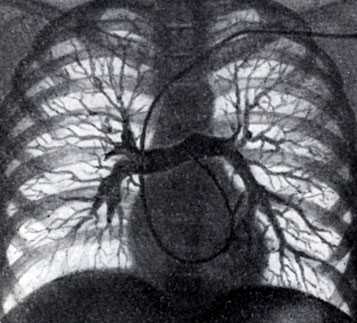

Рис. 2. Селективная ангиопульмонография. Катетер (виден под ключицей, вдоль позвоночника и в области сердца) введен в верхнезональную артерию правого легкого. Видны контрастированные сосуды верхней зоны

Для осуществления общей ангиопульмонографии контрастное вещество в количестве 50—70 мл вводят внутривенно (обычно через локтевую вену) или в полость правого сердца (см. Ангиокардиография) при помощи введенного через вену катетера (рис. 1). При селективной ангиопульмонографии (рис. 2) контрастное вещество вводят в одну из ветвей легочного ствола; для этой цели катетер проводят через правое сердце в легочный ствол и далее в легочную артерию. Для контрастирования одного легкого применяют 20—30 мл контрастного вещества, для исследования одной зоны — 10—15 мл.